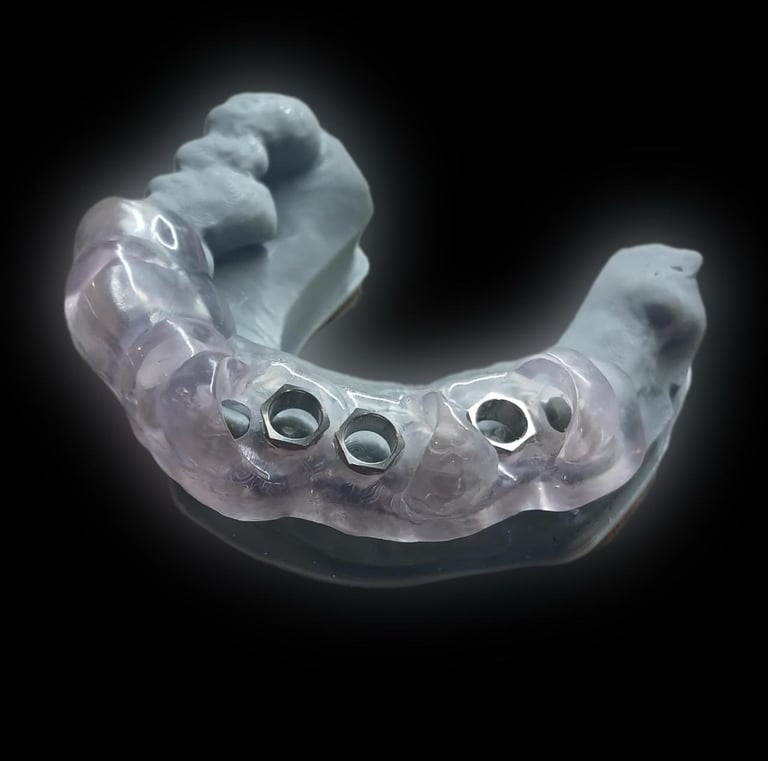

3.A partir del diseño digital, se obtiene una guía quirúrgica para las colocación precisa del implante.